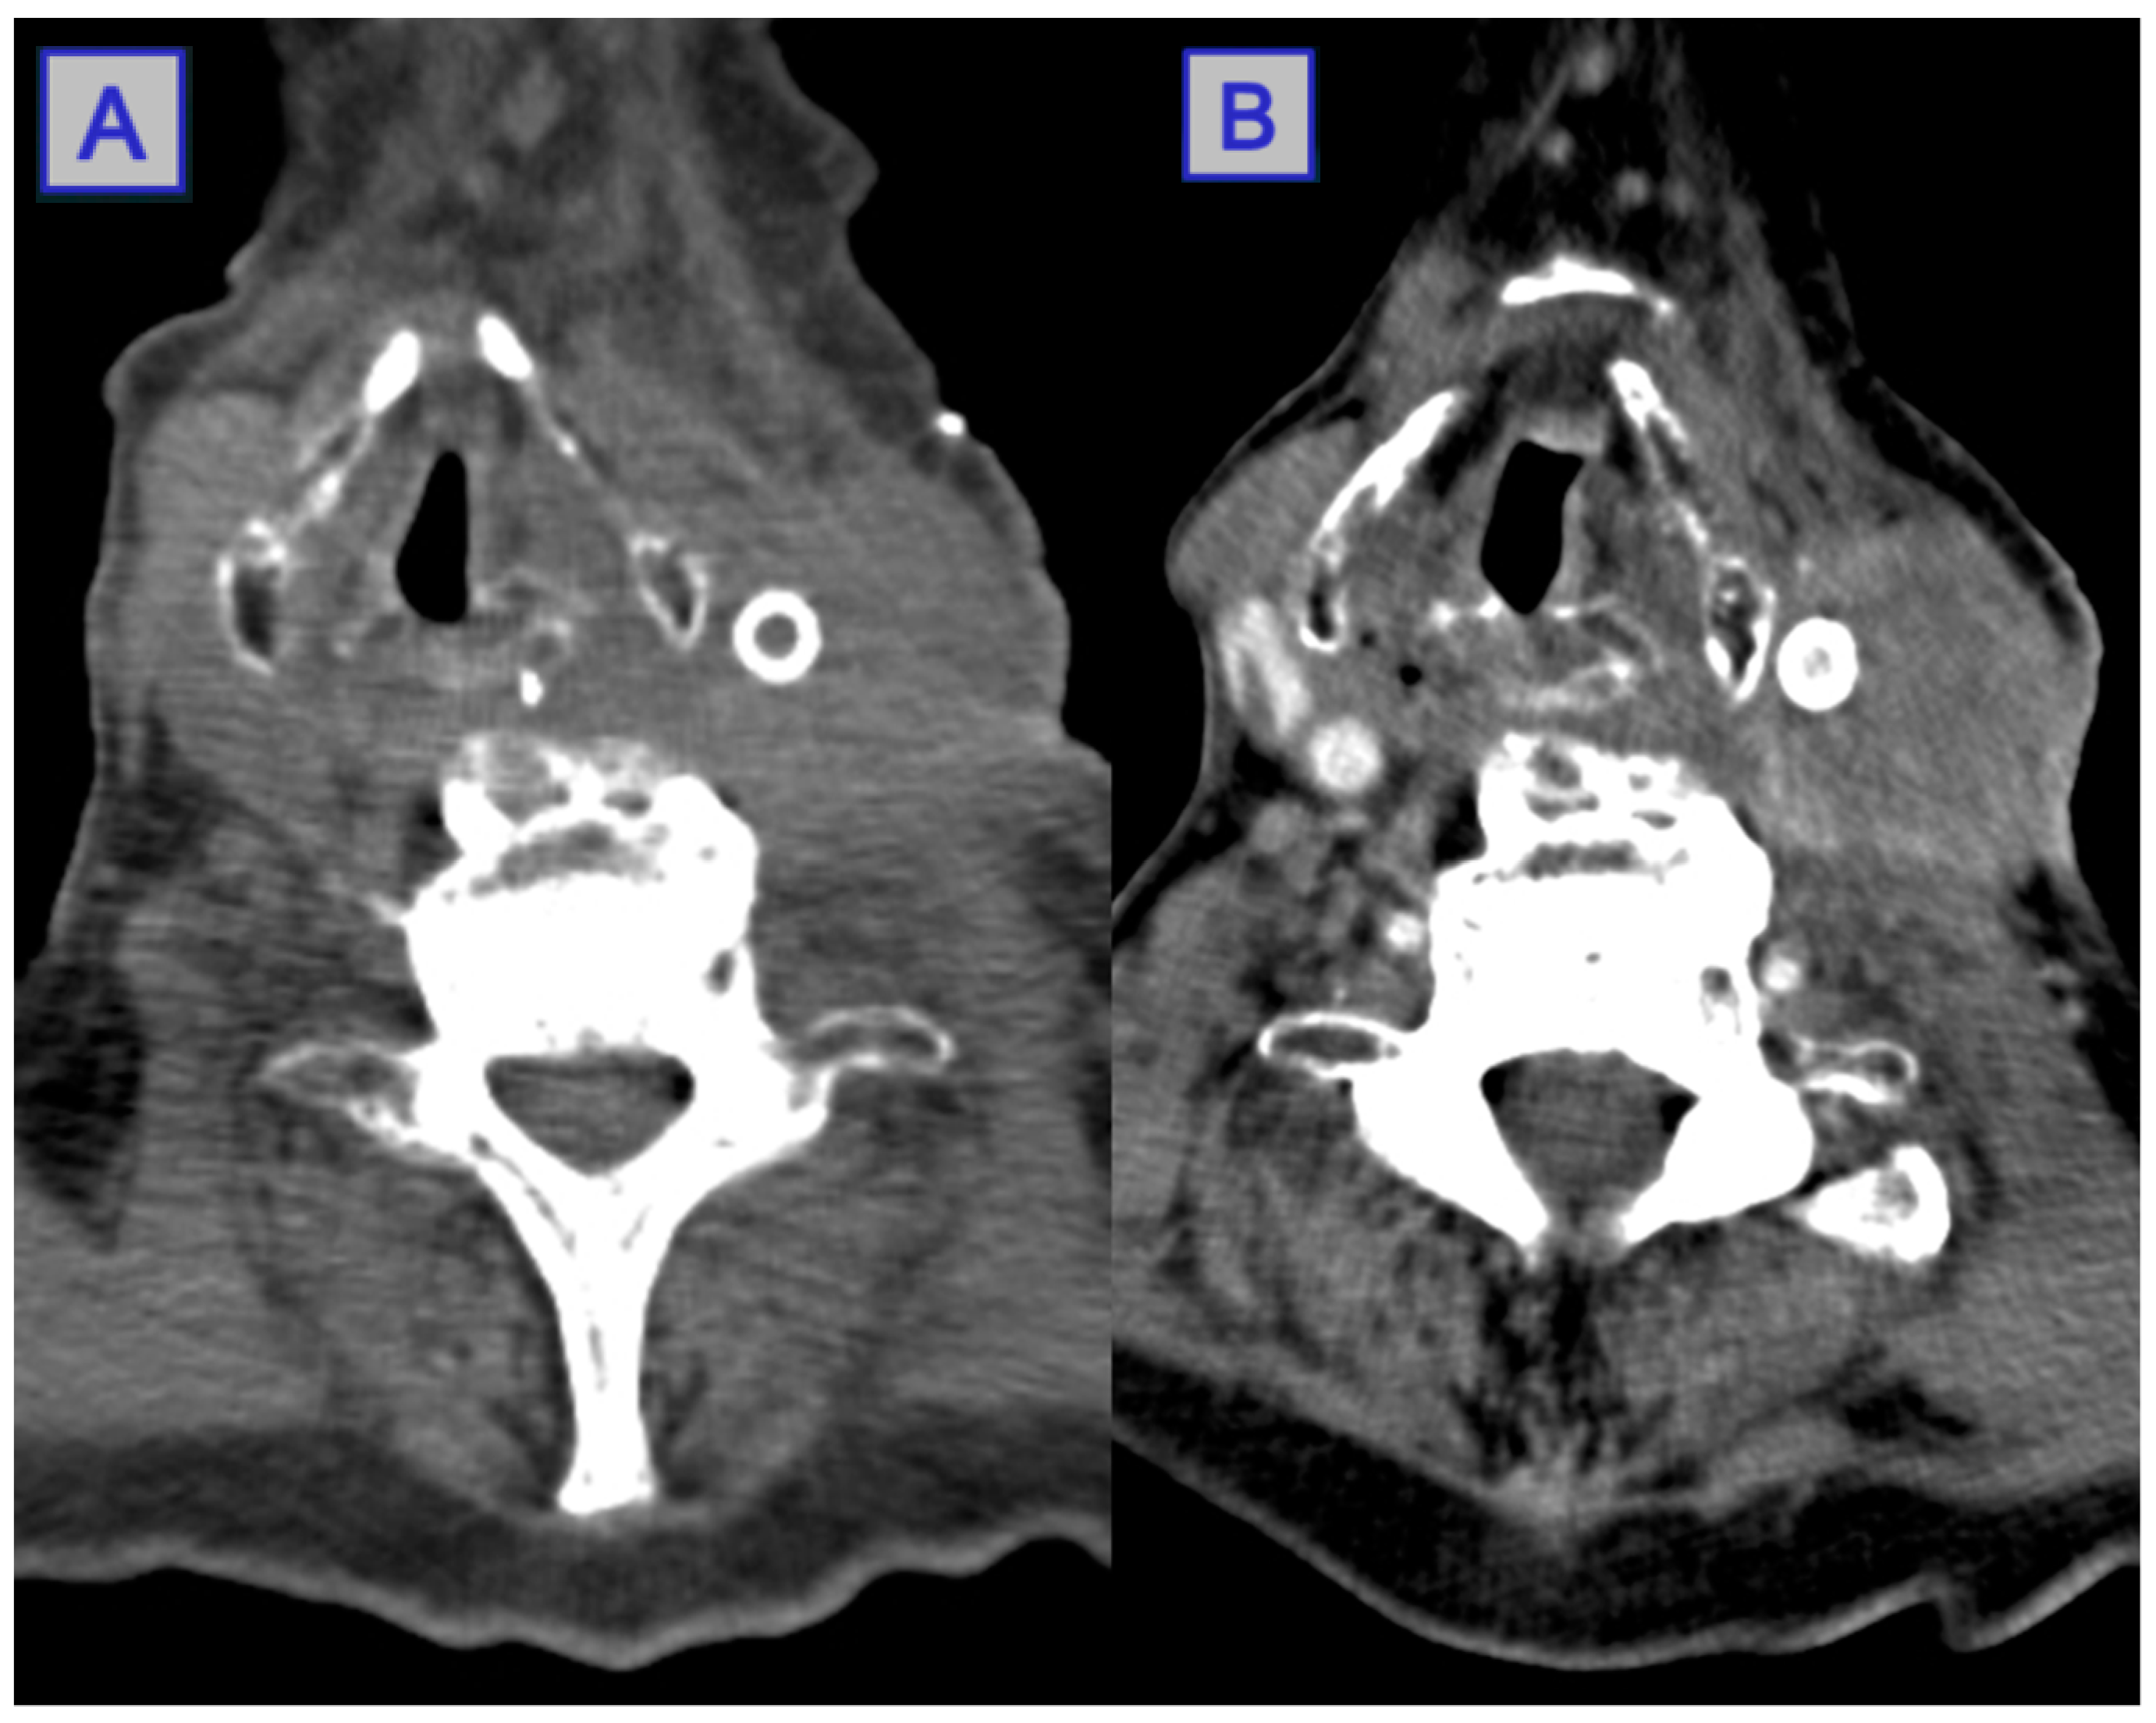

- Jerjes, W.; Upile, T.; Hamdoon, Z.; Mosse, C.A.; Akram, S.; Morley, S.; Hopper, C. Interstitial PDT for vascular anomalies. Lasers Surg. Med. 2011, 43, 357–365. [Google Scholar] [CrossRef]

- Jerjes, W.; Upile, T.; Vincent, A.; Abbas, S.; Shah, P.; Mosse, C.A.; McCarthy, E.; El-Maaytah, M.; Topping, W.; Morley, S.; et al. Management of deep-seated malformations with photodynamic therapy: A new guiding imaging modality. Lasers Med. Sci. 2009, 24, 769–775. [Google Scholar] [CrossRef] [PubMed]